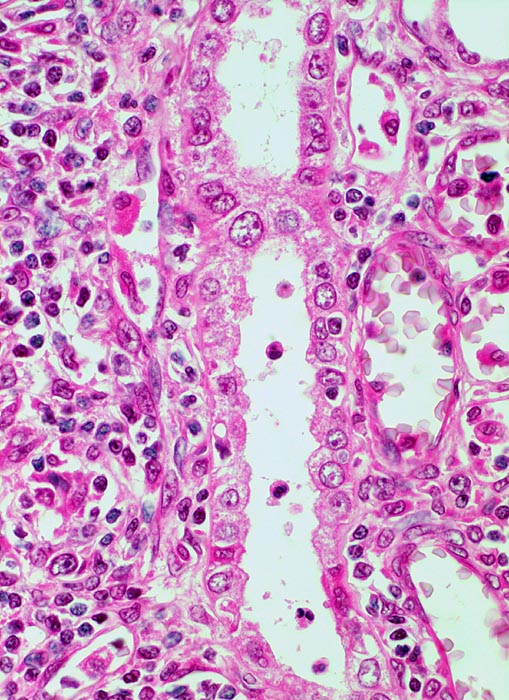

• Akute Abstossung (vorliegendes Präparat):

Typischerweise innert 1 bis 5 Wochen (meist innerhalb der ersten 3 Monate, kann aber jederzeit auftreten) nach Transplantation. Es handelt sich in erster Linie um einen zellvermittelten Prozess mit antigenspezifischer Immunantwort bei Histoinkompatibilität zwischen Spender und Empfänger (Coombs-Typ IV). Bei einem Grossteil der akuten Abstossungen mit Gefässbefall (Endarteritis) und/oder Transplantat-Glomerulitis sind gleichzeitig Antikörper gegen HLA-Antigene nachweisbar. Bei den meisten akuten Abstossungsreaktionen besteht ausschliesslich eine tubulo-interstitielle Entzündung mit Lymphozyten, Histiozyten und später Plasmazellen. Der Prozess ist heute meist reversibel. Histologisch unterscheidet man eine akute tubulointerstitielle, eine vaskuläre, selten eine glomeruläre Abstossung und Mischformen.

Morphologische Merkmale:

• Grosse Biopsie aus Nierenmark und -rinde, letztere mit 13 Glomeruli, alle mit normalem Zell- und Matrixgehalt sowie zarten Kapillarschlingen

• Tubulärer Apparat der Rinde mit ödematös verbreitertem und herdförmig dicht lymphohistiozytär durchsetztem Interstitium

• Vereinzelt Lymphozyten im Tubulusepithel (Tubulitis)

• Eine von 6 grossen bzw. mittelgrossen Interlobulararterien mit segmental verbreiterter, fibrosierter Intima mit Myofibroblasten und mit subendothelial gelegenen Leukozyten (Endothelialitis)